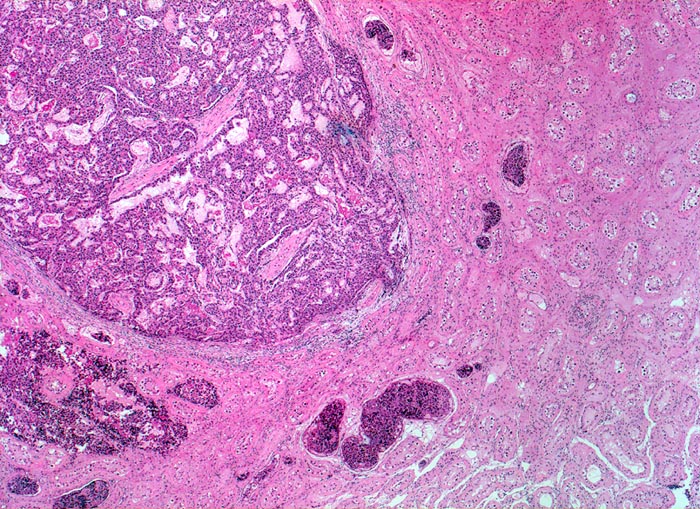

Makroskopisch bilden die embryonalen Karzinome unscharf begrenzte, weiche, graubraune Tumorknoten mit Einblutungen und Nekrosen.

Histologisch bilden die Tumorzellen solide Zellplatten, Drüsen oder papilläre Strukturen mit Einblutungen und Nekrosen. Die Tumorzellen sind polygonal, kubisch oder zylindrisch, haben reichlich Zytoplasma und unscharfe Zellgrenzen. Die grossen Kerne haben grob verklumptes Chromatin und enthalten oft mehrere sehr grosse unregelmässige Nukleolen. Gefässeinbrüche und eine testikuläre intratubuläre Neoplasie sind in der Tumorumgebung häufig nachweisbar